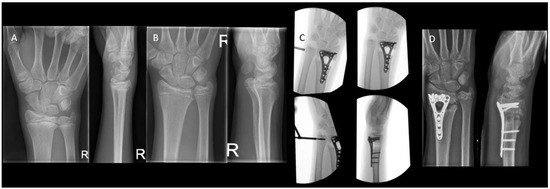

Figure 1. (A) Visual inspection of the carrying angle of the elbow in a 10-year-old girl showing a unilateral cubitus varus on the right side. (B) Anteroposterior radiographic views of the elbow with the unaffected contralateral side for comparison.

Different radiographic angles have been described for the assessment of humeral alignment. The Baumann’s angle is measured on an anteroposterior (AP) radiograph with the elbow in extension. It is formed by the angle between the long axis of the humeral shaft and a straight line through the epiphyseal plate of the capitellum or the lateral condylar physis (Figure 2A). There is a considerable variation in individuals, ranging from 64 to 82 degrees [10,11]. Therefore, the Baumann’s angle is best compared to the contralateral side, where a difference >5 degrees is deemed abnormal.

The lateral capitellohumeral angle (LCHA) is measured on a lateral radiograph as the angle between the line along the anterior surface of the humerus and a line along the open capitellar physis (Figure 2B). The LCHA has a smaller normal range from 45 to 57 degrees and does not vary by age, side, or sex [12] (Figure 2B).

The lateral anterior humeral line (AHL) or capitellohumeral line is a line drawn along the anterior surface of the humerus, which should pass through the middle third of the capitellum on a lateral view (Figure 2C).